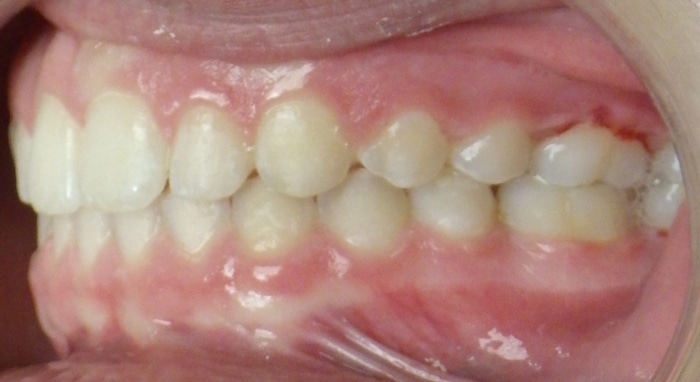

When Marlea presented to us she had a Class II bite with 100% overbite and a 5mm overjet. She also had upper spacing and lower crowding. Marlea’s treatment included metal braces with headgear. With her determination we were able to achieve a Class I bite as well as a perfect overbite and overjet! This is the perfect example of exemplary headgear wear and what a difference it makes in the final outcome of treatment.